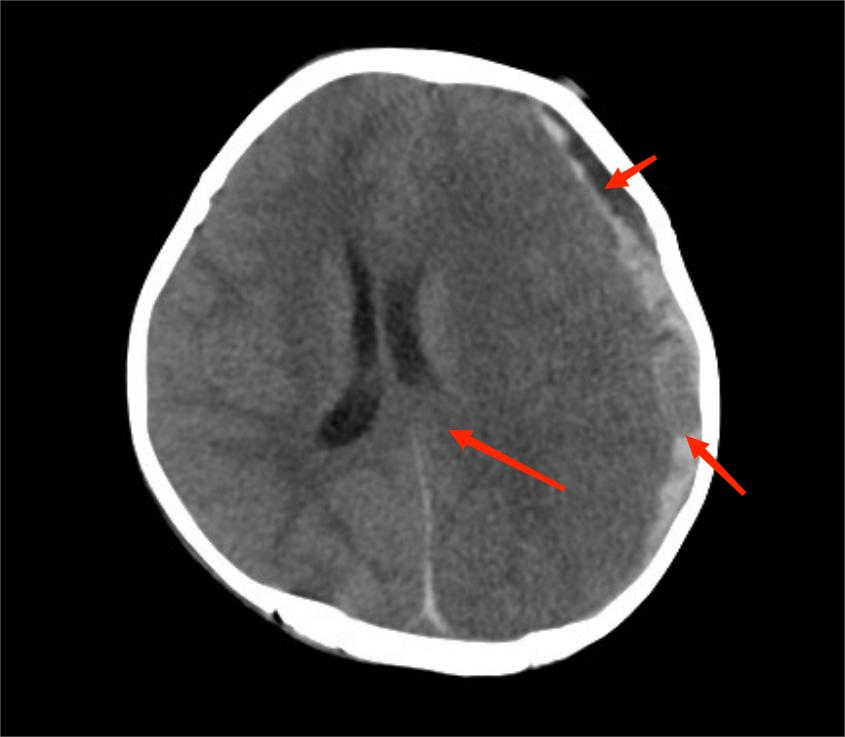

在急诊抢救室,医生发现小尹“双侧瞳孔不等大,对光反射消失”,结合昨天下午她有“摔伤后脑勺”病史,医生判应该“急性颅内出血所致脑疝可能”,紧急查头颅CT提示“硬膜下血肿可能,大脑镰下疝、左侧颞叶钩回疝可能,大脑镰、小脑幕密度增高,蛛网膜下腔出血,枕骨、顶骨骨折,头皮软组织稍肿胀”,考虑“考虑创伤性脑疝”。